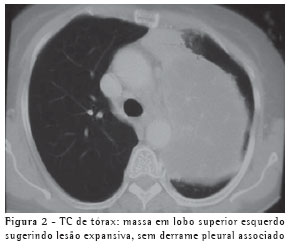

O radiograma torácico apresentava imagem densa, tipo massa, em lobo superior esquerdo (Figura 1). A tomografia computadorizada de tórax (Figura 2) confirmou a presença de massa heterogênea em lobo superior esquerdo, com broncograma aéreo adjacente à mesma, sugerindo lesão expansiva neoplásica. A paciente não conseguiu realizar coleta de escarro para exame devido à pequena quantidade de secreção.

Não há padrão radiológico característico, embora nódulos únicos ou múltiplos, bem definidos e não calcificados, sejam os mais comuns, podendo simular radiologicamente neoplasia.(5,9) Foram descritas alterações radiológicas tais como infiltrado (62%), nódulos (38%), massa (19%), lesão cavitada (14%) e derrame pleural (3%), sem um padrão de distribuição anatômica e sem adenomegalia hilar ou mediastinal associados. Há relatos na literatura de empiema, pneumotórax e envolvimento pleural sugerindo tumor de Pancoast(13) e massa pulmonar invadindo parede torácica.(14) A tomografia computadorizada de tórax corrobora os achados radiológicos, fornecendo maiores detalhes para o diagnóstico diferencial(11) e, quando necessário, auxilia na programação da propedêutica diagnóstica invasiva. A paciente descrita apresentava massa pulmonar simulando neoplasia.